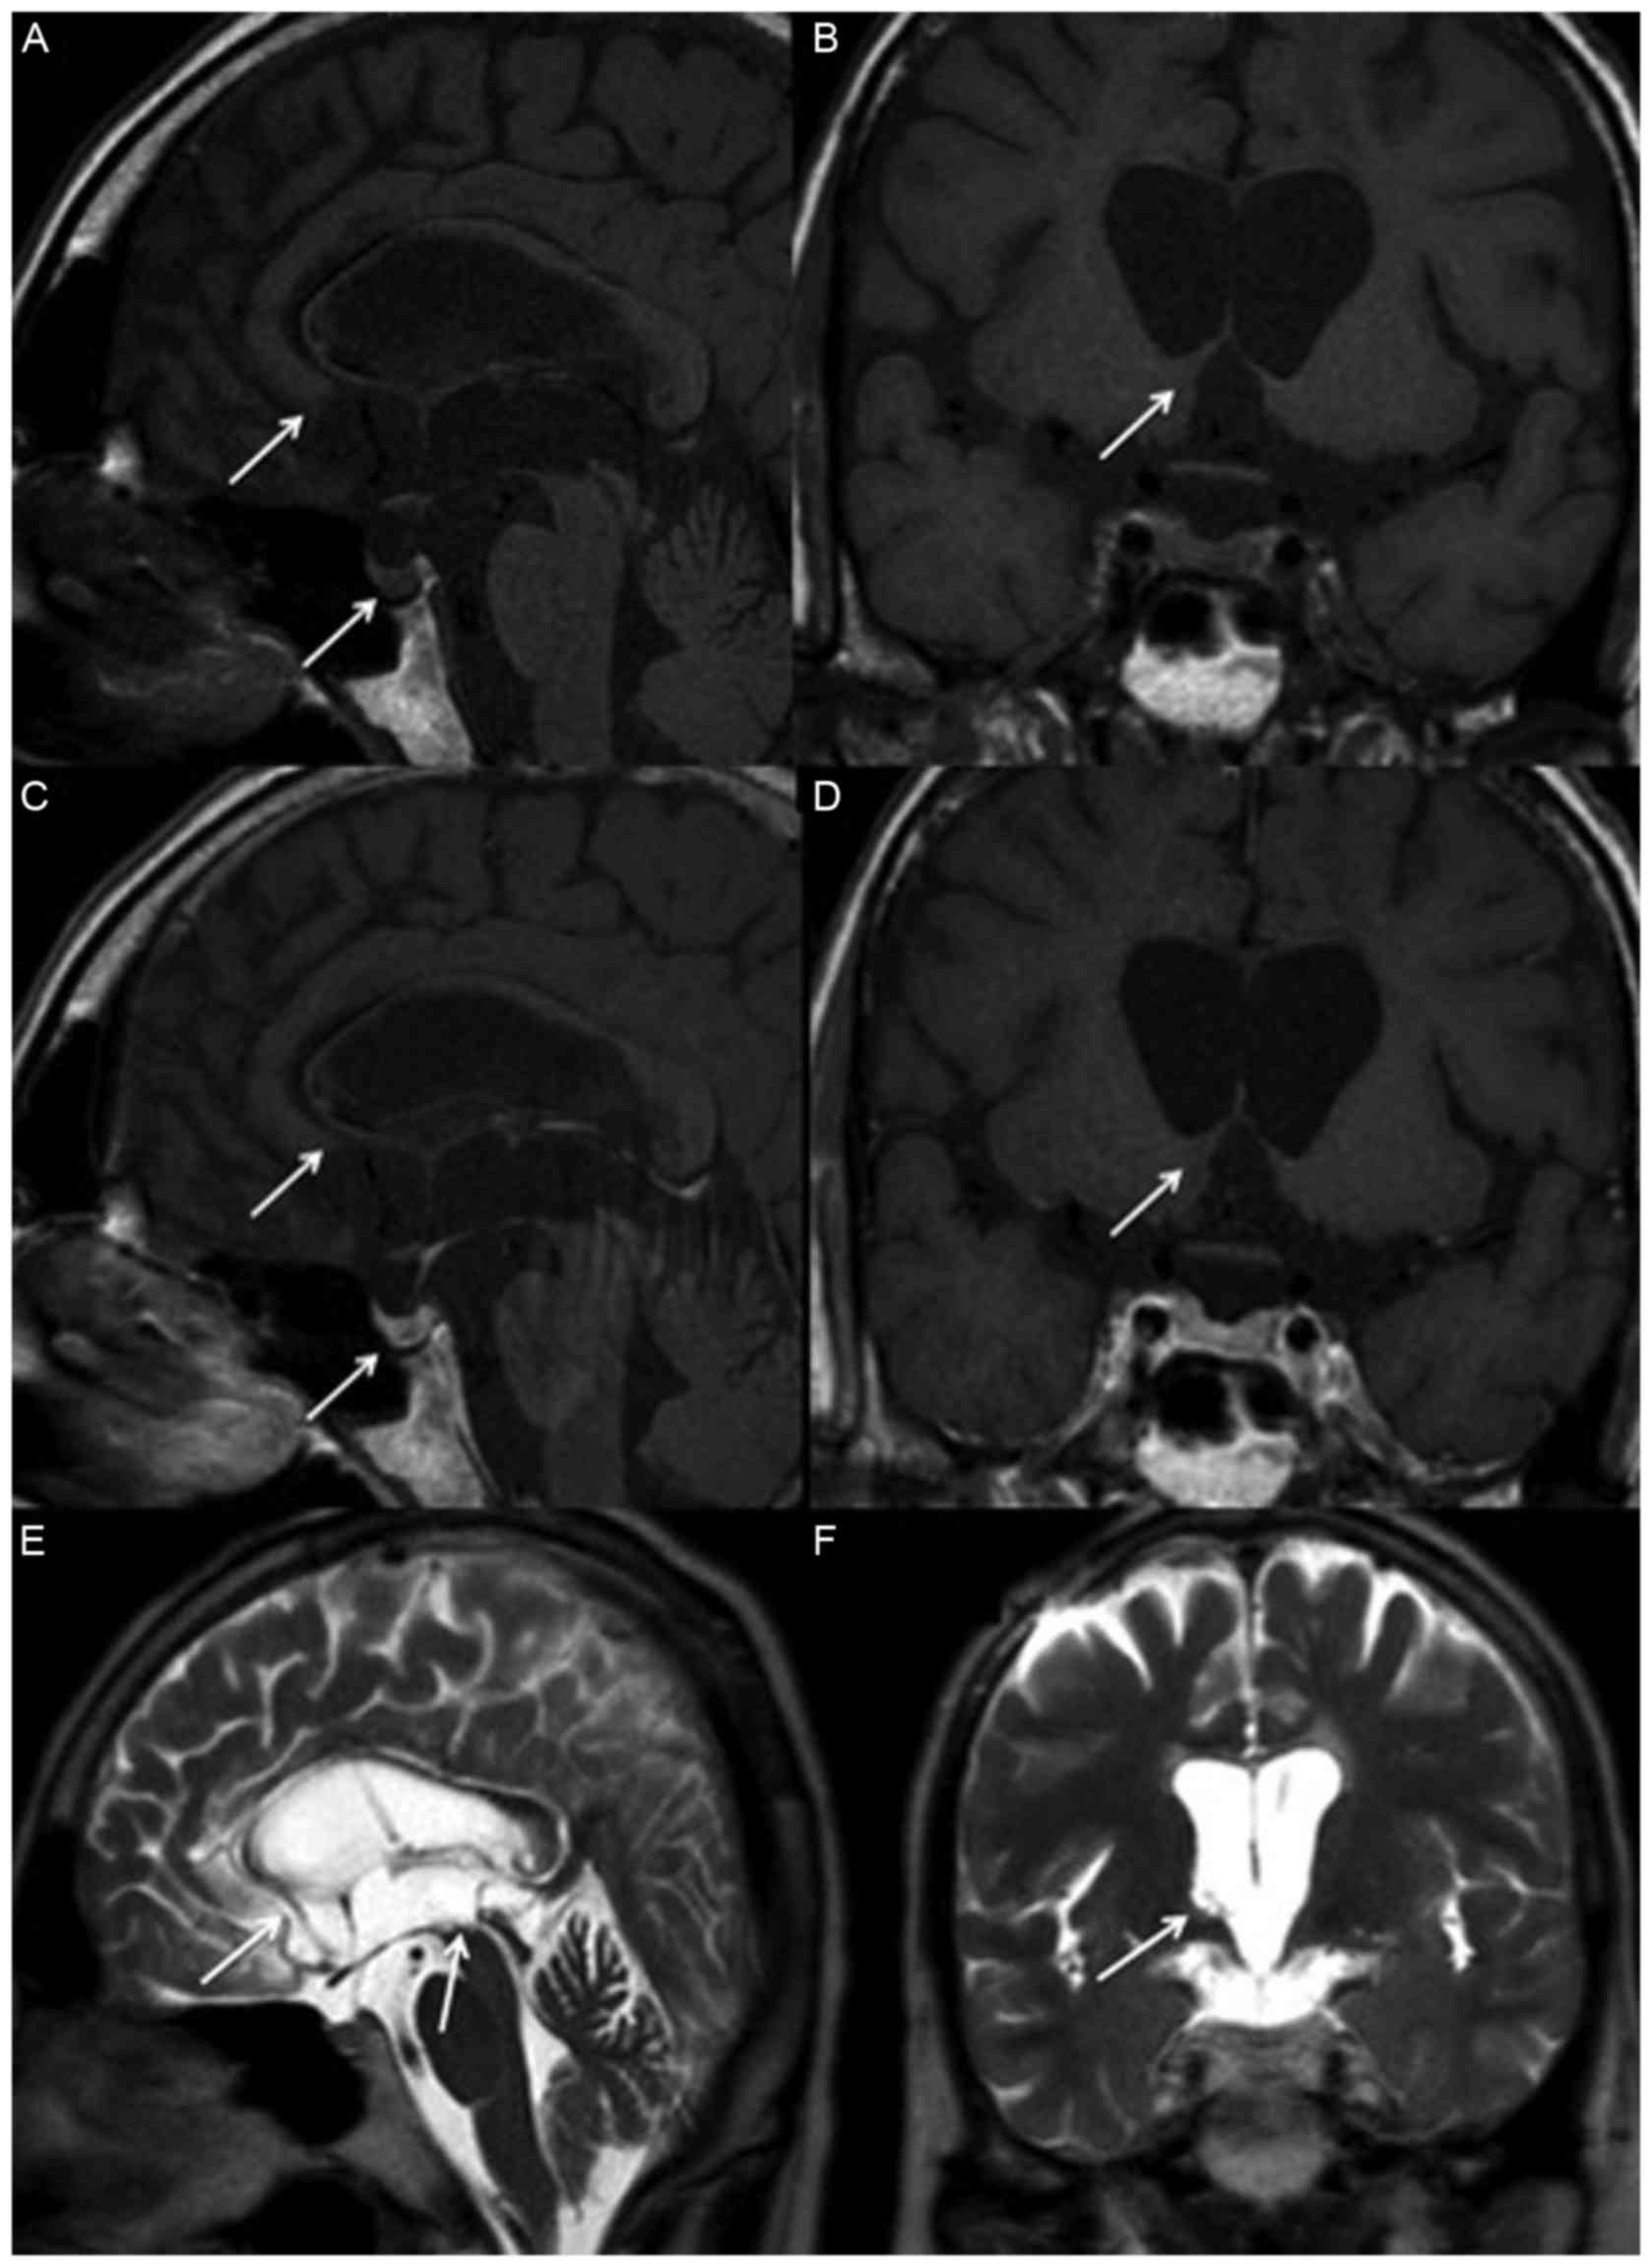

A brain MRI scan revealed the presence of a heterogeneous lesion involved in the right basal ganglion, hypothalamus, and the extension to the corpus callosum and to the posterior hippocampus. The pineal gland, stalk and posterior pituitary gland were also involved (Fig 1). A lumber puncture was performed and CSF cytology revealed no malignant cells, but CSF β-hCG levels of 1,936 IU/l and AFP levels <0.24 ng/ml. The serum AFP level was 3.28 ng/ml, and the β-hCG level was 178 IU/l, with a CSF:serum β-hCG ratio >2:1. Neck to pelvis computed tomography excluded the presence of metastatic lesions. It was not possible to obtain a pathological diagnosis due to the deep location of the tumors. However, a β-hCG secreting suprasella GCT was suspected due to imaging and tumor markers.

Figure 1.

Magnetic resonance imaging of sella prior to treatment. Heterogeneous lesions are indicated by arrows and are present in the basal ganglion, hypothalamus, corpus callosum, posterior hippocampus, pineal gland, stalk and posterior pituitary gland in (A) non-contrast sagittal, (B) coronal, (C) contrast sagittal and (D) coronal T1 weighted images, as well as (E) T2 weighted sagittal and (F) coronal images.